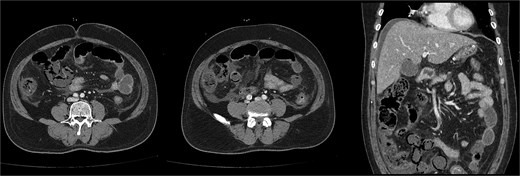

Due to severe bowel ischaemia, he underwent emergency surgery on the second day, including right hemicolectomy and SB resection, resulting in double-barrel ileocolostomy. The resected and remaining portions of SB measured ~200 cm (Fig. 3).